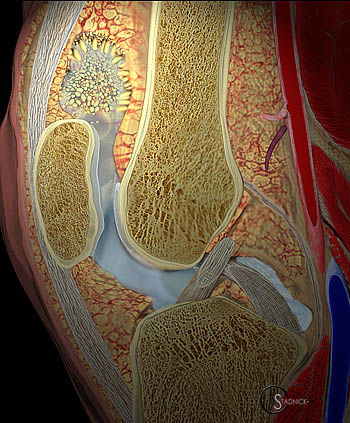

Рисунок 1. Арборесцентная липома. Макропрепарат.

Древовидная (арборесцентная) липома (ДЛ) — редкое заболевание суставов, которое заключается в синовиальной пролиферации зрелых адипоцитов. Название «древовидная» (или ветвистая) дано этой опухоли из-за особенностей макроскопического строения: неправильной формы конгломерат жировой ткани очертаниями напоминает ветвистое дерево, покрытое листьями. В случае «давнего» патологического процесса адипоциты могут инфильтрировать и подсиновиальную соединительную ткань.

Рисунок 2. Схема сагиттального среза коленного сустава с древовидной липомой: листовидные, дольчатые разрастания синовиальной оболочки в надколенном завороте.